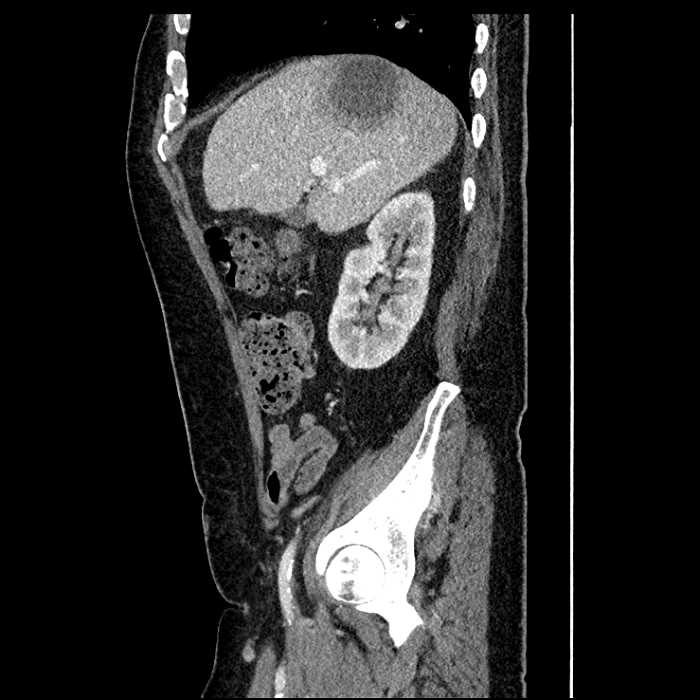

• Large fluid density structure in hepatic segments 7 and 8 measuring 10 x 7 x 7 cm with internal septation and circumferential ill-defined low density compatible with edema

• Peripherally enhancing subcapsular collections along the anterior margin of the left hepatic lobe measuring 3 x 1 cm and 2 x 1 cm

• Clearly marginated fluid density structure in segment 7 and several other scattered tiny hypodensities, which likely represent cysts

• Hepatic abscess

Acute sigmoid diverticulitis complicated by a small contained perforation and a large abscess in the right hepatic lobe. Additional small subcapsular abscesses along the anterior margin of the left hepatic lobe.

• The classic CT imaging appearance is a double target sign with internal low density surrounded by an internal enhancing rim (capsule) and a low density external rim (edema)

• Abscesses may be unilocular or multilocular

• Gas is present in a minority of cases

Hepatic abscess showing the double target sign with low density internally surrounded by a thin inner enhancing rim (red arrow) and ill-defined outer low density rim (yellow arrow). Blue arrow indicates an internal septation. Red arrows: additional smaller subcapsular abscesses. Red arrow: focal contained perforation associated with diverticulitis.